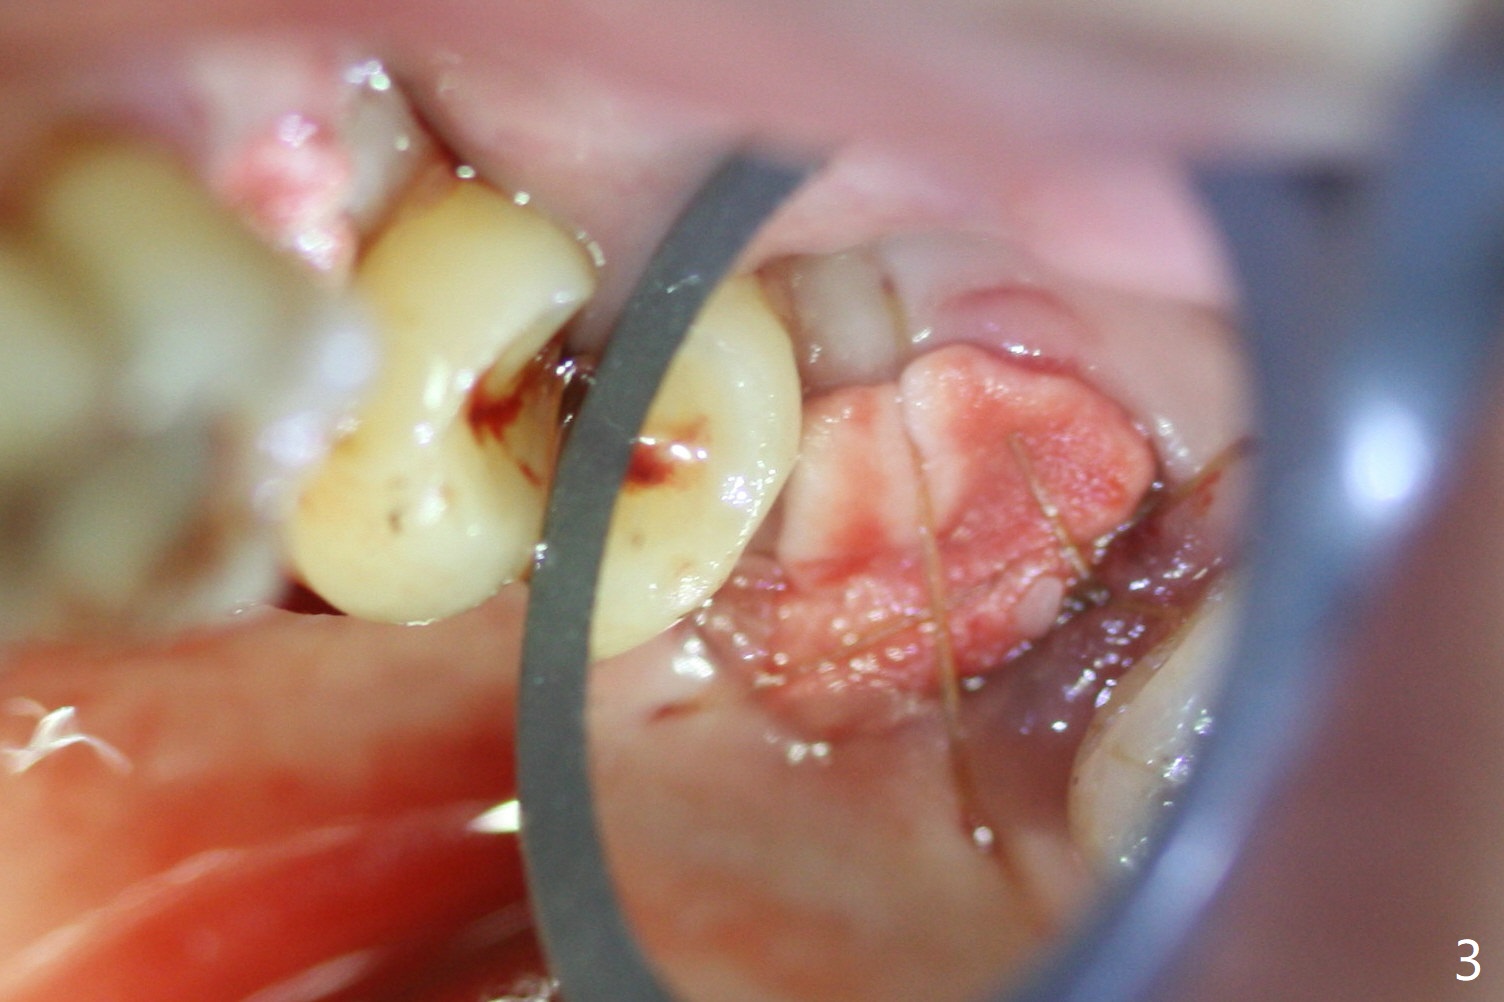

A cover screw is used, followed by allograft (Fig.1 *).  The latter is covered with another piece of PRF membrane, collagen membrane (Fig.3) and periodontal dressing.